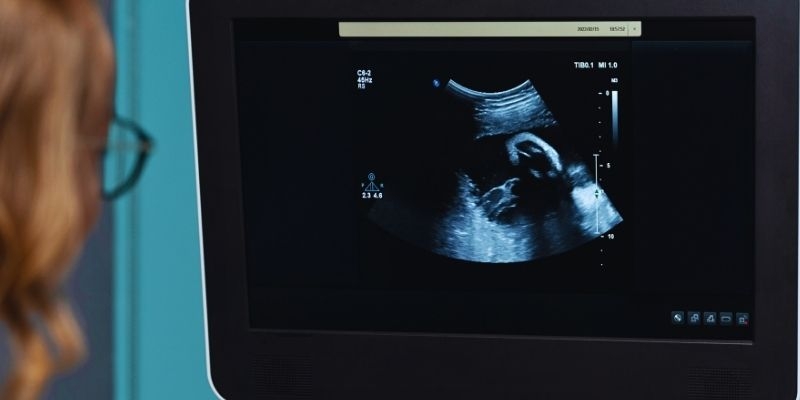

73 yaşındaki kadının midesinin röntgeni sonrası, yedi aylık ve 4,5 kilo ağırlığında taÅŸ fetüs olduÄŸu tespit edildi.